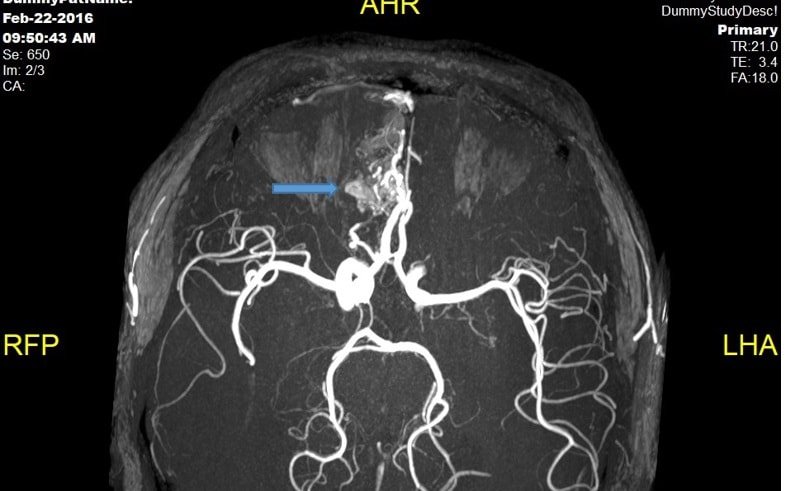

Đi khám, trẻ 14 tuổi mới biết mắc bệnh lạ

PLBĐ- Ths. BS Phạm Gia Dự - Khoa Ngoại thần kinh, Bệnh viện K thông tin về trường hợp bệnh nhân Nam (14 tuổi) là con đầu trong gia đình có 3 con, được chẩn đoán mắc bệnh xơ cứng củ.